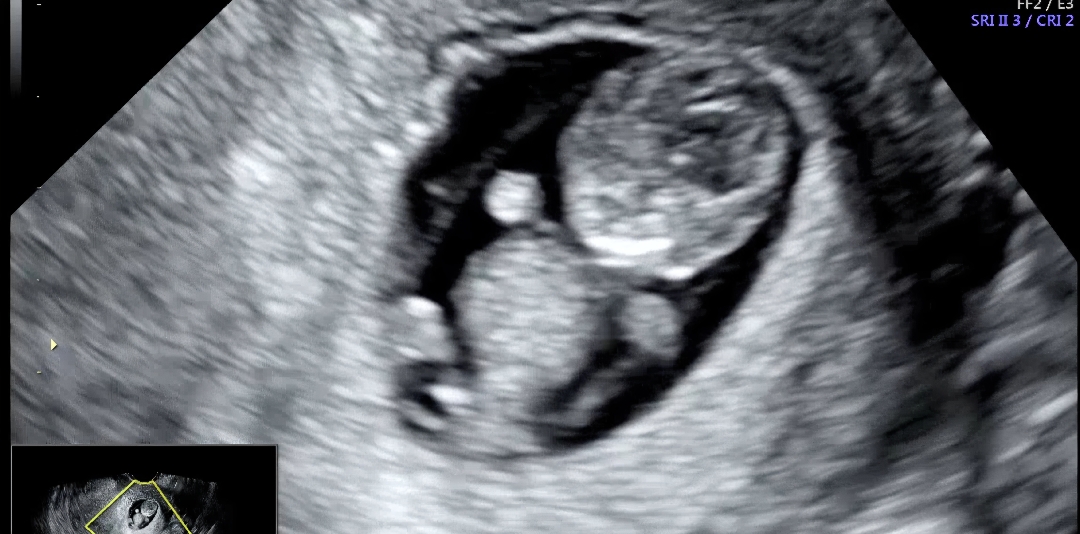

9주1일차 초음파 보고왔어요!

8-9주수차에 다들 말씀하시는 젤리곰 보고왔어요 🫶 꼬물꼬물 짧은 팔다리 ㅋㅋㅋㅋ 얼마나 귀엽던지.... 의사쌤이 이건꼭보고가야한다면서 배도 살살흔들고 기침도 해보라고하더니 꼬물꼬물 뱃속에서 팔다리흔들며 춤추는거 보고왔네요 ㅎㅎㅎ 진짜 너무너무 귀여웠어요 도치맘 예약입니다ㅋㅋㅋ🫠 언능 3주 지나서 또 만나고싶어요 🥰 임신때문에 몸힘든거 싹 잊혀지는 순간이었습니다 ! ㅎㅎ